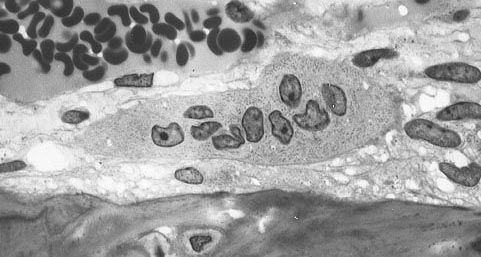

Figure 6.32: Bone marrow derived cells with bone below it showing the typical distinguishing characteristics of the osteoporosis cells: large cells with multiple nuclei and a `foamy' cytosol.